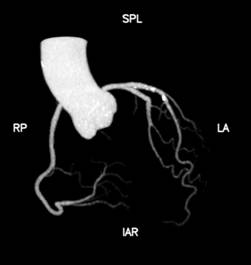

1、心脏检查时无需屏气,无需服药控制心率

Apex CT拥有160mm超宽体探测器,旋转一周仅需0.28s,即可以在一个心动周期内完成整个心脏的扫描。患者无需提早一小时来服药控制心率,高心率、房颤室颤、无法配合呼吸的患者都能在自然状态下接受检查,并通过高能量子球管使用的低kV高mA的扫描模式,在降低对比剂速率、用量和辐射剂量的同时,还能提高组织对比度,得到更高的密度分辨率,显示出更清晰的病灶。